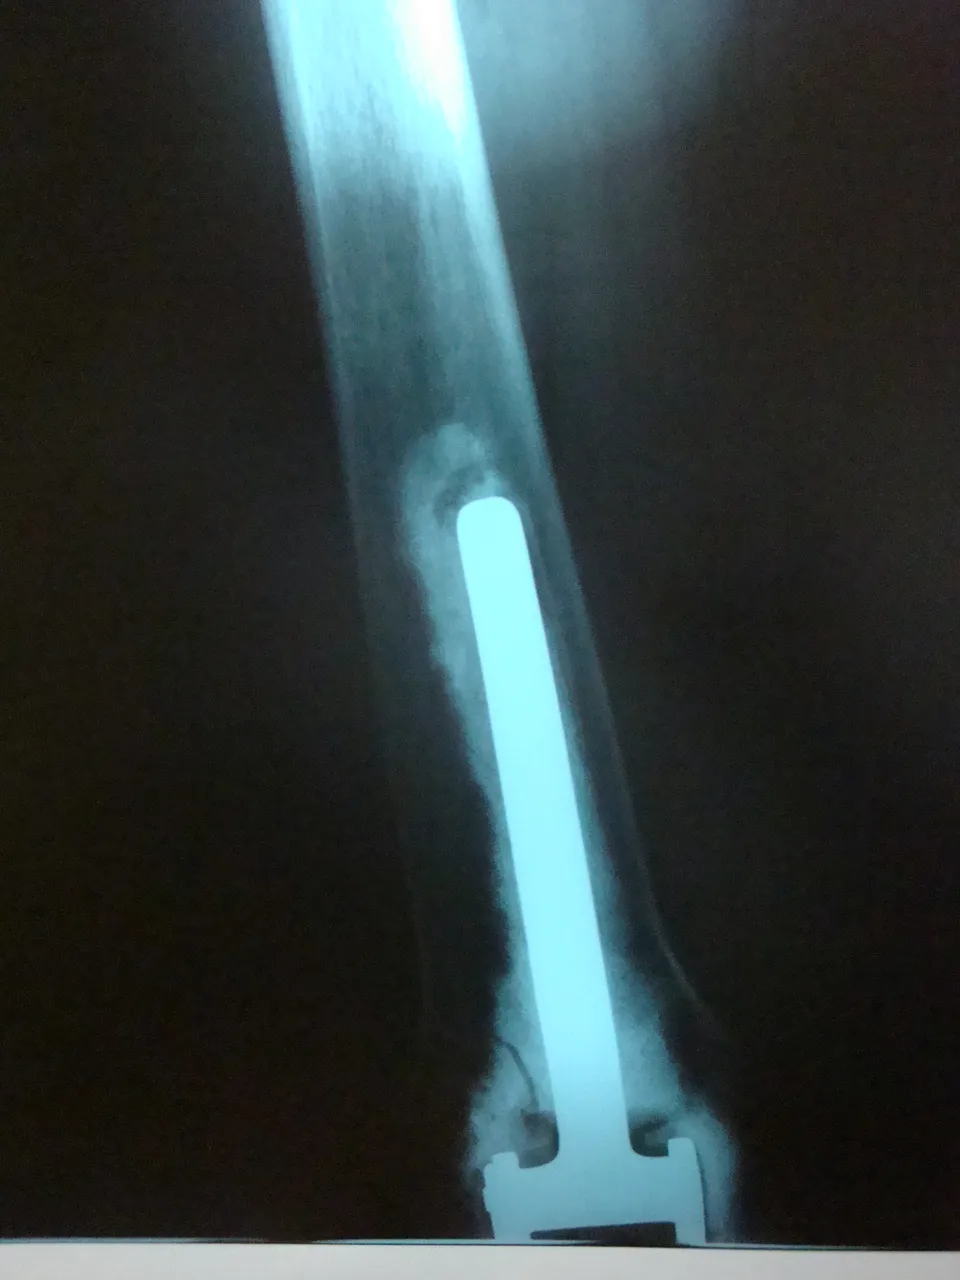

The total knee prosthesis is the reference technique when the tumor is aggressive, extracompartmental and extends to the epiphysis. A constrained total prosthesis is used, preferably a "forced fit", cemented, with long centromedullary stems that rest on the isthmus of the healthy side. The joint is a hinge with or without rotation. When the affectation is femoral without joint invasion, if a subtotal excision of the quadriceps is made, special care must be taken in the reconstruction of the extensor apparatus by means of transfer of the hamstrings.

In femoral tumors, reconstruction is done with a vascularized fibula that is placed in the medial part, with a complementary lateral allograft. Osteosynthesis is done with a plate. In tibial tumors, an allograft maintained with a bolted nail is an effective solution. At present, arthrodesis is restricted to rare cases such as patients with high sports activity or demanding jobs or if there is a risk of significant infection; they are performed with the help of an inverted vascularized fibula. The current therapeutic guidelines are characterised by the reduction of arthrodesis and by the use of prostheses that have demonstrated their longevity and functionality. The recommendation of biological therapies rests on their longevity, as long as they are compatible with a satisfactory oncological removal. This exeresis and reconstruction surgery provides good oncological results, although at the cost of complex interventions that involve frequent substitutions. Only teams familiar with replacement prostheses and the practice of flaps and experts in vascularized bone transfers should make it.